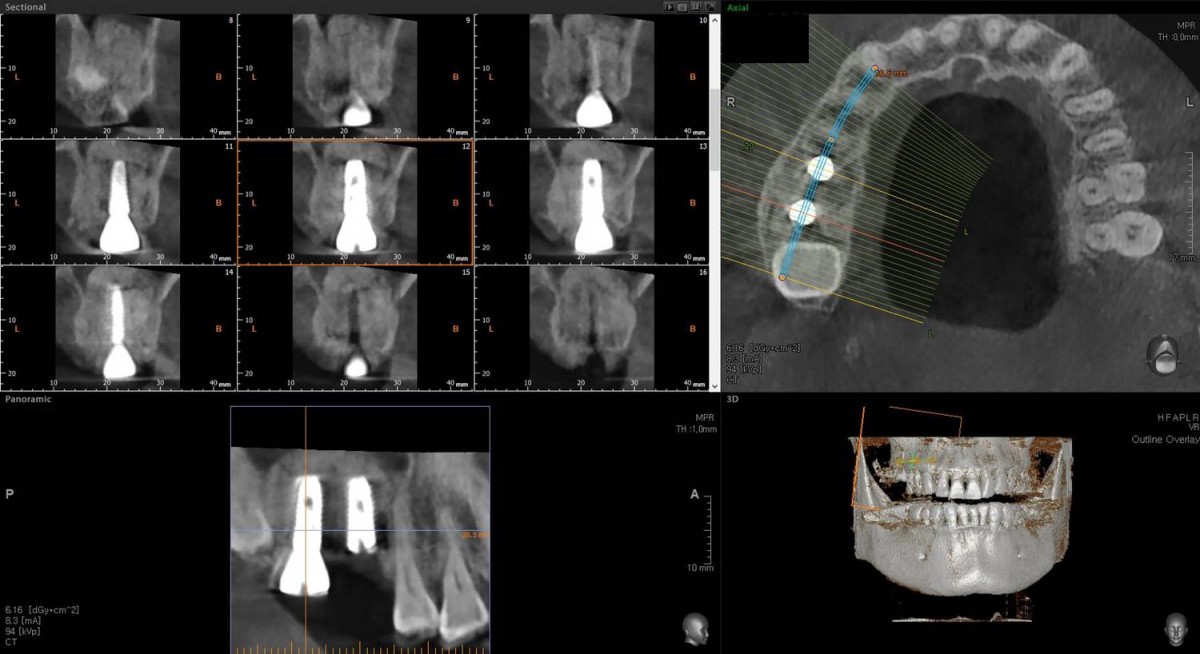

Maxillary Sinus Graft, 2 Implants, Crown Contouring

<GCaks> A 56-year-old male patient had pain-inducing caries, and perio-involved tooth mobility resulted in a tooth fracture at 1st molar. And it was removed months ago. He was a heavy smoker and showed poor oral hygiene.